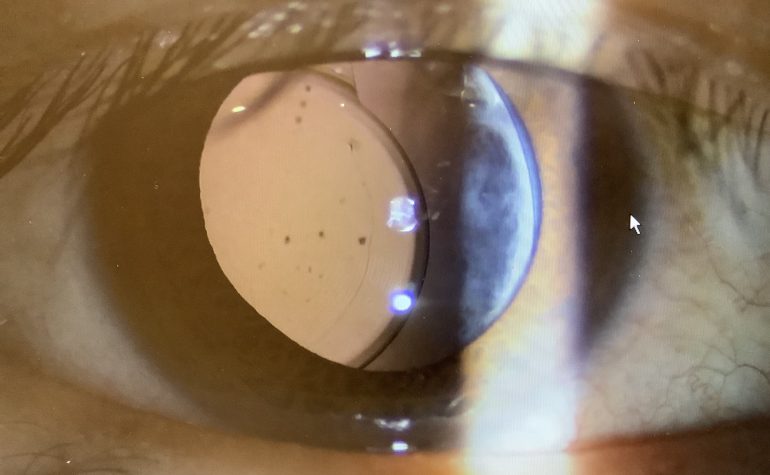

眼内レンズは眼の中で“水晶体嚢”という水晶体の周りの透明な袋の中に入れてきますが、この水晶体嚢は“チン小帯”という細い線維で眼の壁に固定されています。

よく白内障手術の患者さまから『レンズがズレてしまうことはないのですか?』と質問されることがありますが、その答えは『ズレることもあります』です(ここでいう、ズレは度数のことではなく、位置が悪くなってしまう物理的なズレのことです)。もちろん、皆んながみんなレンズがズレるということはなく、ほとんどの方は大丈夫です。しかし、ある一定数の患者さまで眼内レンズがズレる“眼内レンズ偏位”という状態が起きてしまいます。その原因は、先ほど触れたチン小帯が弱いことがあるからです。元々、先天的に、もしくは体質的に弱い人もいますし、外的な要因、例えば、眼のケガやアトピーで眼を掻いてしまう人などでもチン小帯が弱くなりやすい傾向があります。

眼内レンズ偏位が起こると、レンズの位置が中心から外れたり、ゆらゆら動いたり、前後方向に傾くこともあり、見え方がおかしくなります。見えるときもあるけれど、見えにくい時もあると感じたり、揺れるような見え方をしたり、光がおかしくみえることもあります。

↑ズレた眼内レンズ